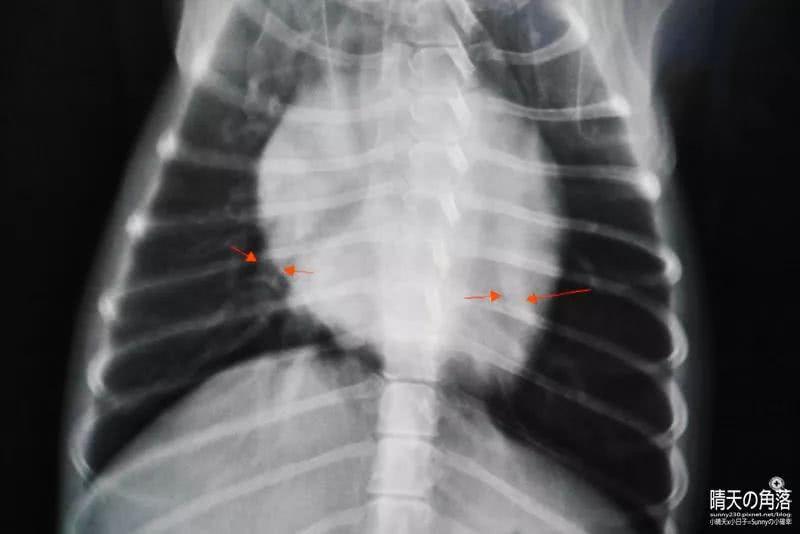

大部分确诊心脏病的狗狗, 都是因为主人们误以为它们感冒了